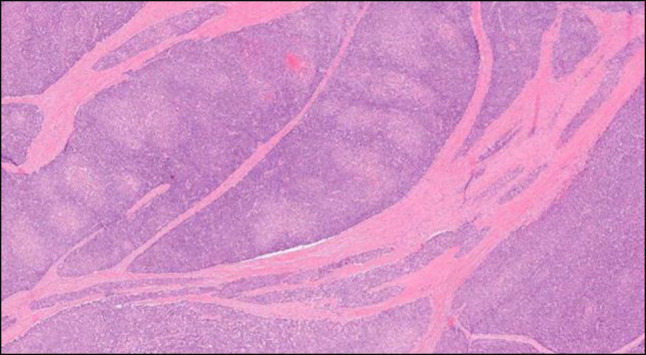

胰腺母细胞瘤(PB)是一种极其罕见的胰腺组织恶性肿瘤,占所有胰腺肿瘤的不到1%。由于罕见的恶性肿瘤和潜在的多种鉴别诊断,成人发病的PB可能是具有挑战性的诊断。诊断成人PB的主要特征是组织学。约90%的病例可见鳞状小体。我们提出一个病例的患者诊断为成人发病的PB,谁提出了关键的临床和病理特征,以及罕见的特征,与恶性肿瘤相关。

Pancreatoblastoma (PB), an extremely rare malignancy of the pancreatic tissue, comprises less than 1% of all pancreatic tumors. Owing to the rarity of the malignancy and the potential for multiple differential diagnoses, adult-onset PB can be challenging to diagnose. The hallmark characteristic in diagnosing adult PB is found histologically. In approximately 90% of cases, squamous corpuscles are observed. We present the case of a patient diagnosed with adult-onset PB, who presented with key clinical and pathological features, as well as rarer characteristics, associated with the malignancy.